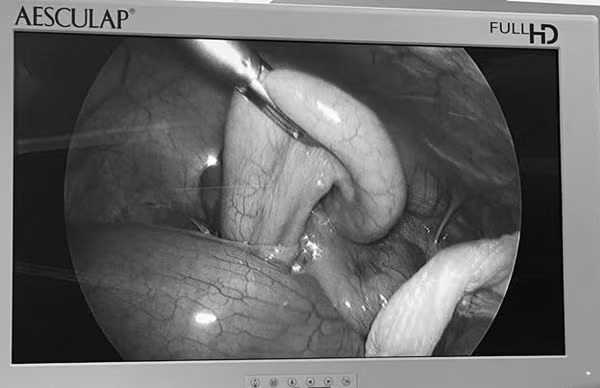

| Viêm ruột thừa cấp trên hình ảnh nội soi - Ảnh BVCC |

Bệnh nhân nhanh chóng được bác sĩ chẩn đoán: Viêm ruột thừa cấp và chỉ định thực hiện phẫu thuật cắt ruột thừa bị viêm bằng phương pháp nội soi.

Các bác sĩ khoa Ngoại, khoa Phẫu thuật – Gây mê hồi sức khẩn trương chuẩn bị dụng cụ để phẫu thuật cấp cứu bệnh nhân Đ.T.K. BS Nguyễn Minh Chắc và BS Vũ Trung Hiếu, khoa Ngoại trực tiếp phẫu thuật, trong phẫu thuật các chuyên khoa phối hợp chặt chẽ với nhau đã kịp thời cứu sống bệnh nhân trong gang tấc. Sau 1 giờ đồng hồ ca phẫu thuật đã thành công.